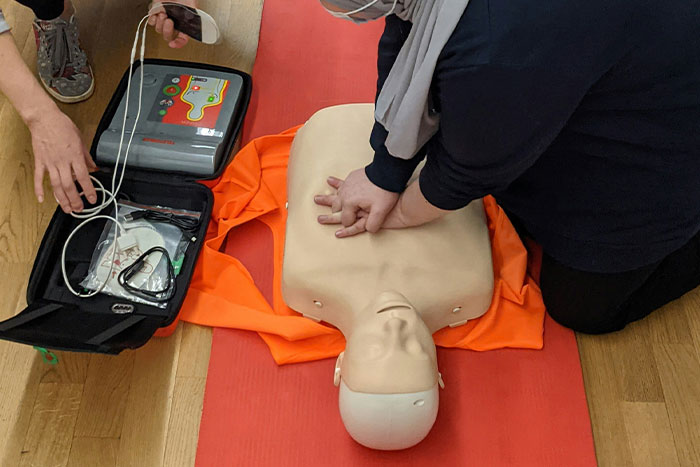

#36

Chest compressions are violent. Just let your 91 year old grandma go.

Image credits: Shomer_Effin_Shabbas